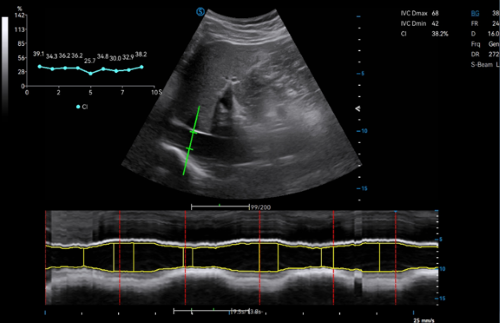

· Auto Inferior Vena Cava (Auto IVC) is a standardized measurement for quick analysis of right atrial pressure and fluid status in ICU to determine abnormal blood volume and cardiac stress. It automatically detects, tracks and measures the IVC for rapid diagnosis.